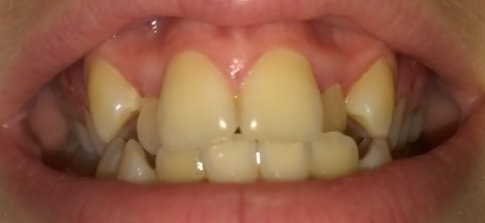

Мне 31 год. У меня кривые передние зубы, в детстве не задумывался. Сейчас чувствую себя не в своей тарелке. Хочу кривые зубы вырвать и вставить не съёмные импланты. Хочу узнать цену, и стоит ли это делать?

• Необходим осмотр и панорамный рентгеновский снимок зубов. Удалять здоровые зубы не нужно. У Вас, по фото, скученность зубов из-за нехватки места в зубном ряду и недоразвитие челюстных костей. Следовательно, и неправильный патологический прикус. В таком случае, требуется лечение брекет-системой. Проконсультируйтесь очно со стоматологом-ортодонтом для составления плана лечения.